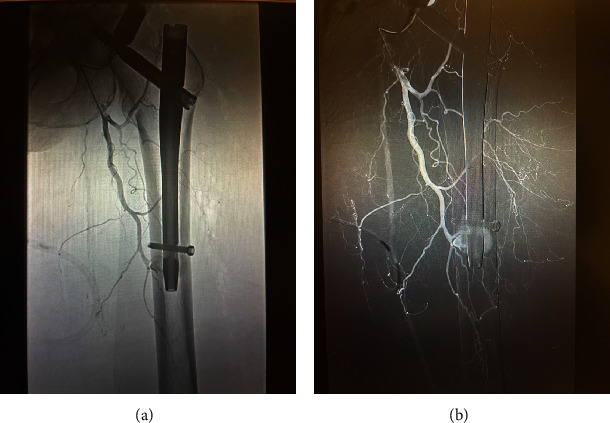

介绍:髋关节转子间骨折的手术治疗是一种常见手术,术中并发症发生率较低。在不切开复位的情况下放置髓内钉,血管损伤非常罕见。在髋部骨折闭合复位和髓内钉置入术后,远端联锁螺钉水平出现直接动脉损伤和活动性出血的病例极少见。我们报告了一例这样的病例。病例介绍:一名 88 岁的女性因左侧转子间髋部骨折到急诊科就诊。按计划对左侧髋部骨折进行了闭合复位并用头髓内钉固定,术中没有出现任何明显的技术问题。术中患者病情保持稳定。无需进行切开复位。术后,患者出现失血性休克,需要大量输血。血管造影显示,髓内钉远端锁定螺钉处出现肌肉内血肿,并伴有活动性外渗。患者随后需要进行栓塞治疗。术后九天,她开始服用伊利奎斯(Eliquis)预防深静脉血栓形成,目前已能独立行走,血肿也有消退迹象。讨论股深动脉损伤可能源于手术过程中的各种机制。动脉粥样硬化会使患者因血管僵硬而面临更高的并发症风险。在本病例中,钻孔超出股内侧皮质被认为是导致动脉损伤的原因。结论:在手术过程中应注意防止钻头陷入股内侧皮质之外。谨慎观察患者的生命体征和临床病程可及早发现血管并发症。

Introduction: Surgical management of intertrochanteric hip fractures is a common surgery with low rates of intraoperative complications. Vascular injuries are exceptionally rare when placing an intramedullary nail without open reduction. There are very few reported cases of direct arterial injury and active bleed at the level of the distal interlocking screw following closed reduction and intramedullary nailing of a hip fracture. We report one such case. Case Presentation: An 88-year-old female presented to the emergency department with a left intertrochanteric hip fracture. Closed reduction with a cephalomedullary nail fixation of the left hip fracture occurred as planned without any obvious intraoperative technical issues. The patient remained stable intraoperatively. No open reduction was required. Postoperatively, the patient developed hemorrhagic shock and required massive transfusion protocol. Angiography demonstrated an intramuscular hematoma at the level of the distal intramedullary nail interlocking screw with active extravasation. The patient subsequently required embolization. Nine days following surgery, she began Eliquis for DVT prophylaxis and was ambulating independently with signs of hematoma resolution. Discussion: Profunda femoris artery injury can stem from various mechanisms during surgery. Atherosclerosis places patients at a higher risk of complication due to rigid vessels. In this case, it is believed that drilling beyond the medial femoral cortex led to the arterial injury. Conclusion: Care should be taken to prevent drills from plunging beyond the medial femoral cortex during surgery. Cautious observation of patient's vitals and clinical course can allow for early detection of vascular complication.